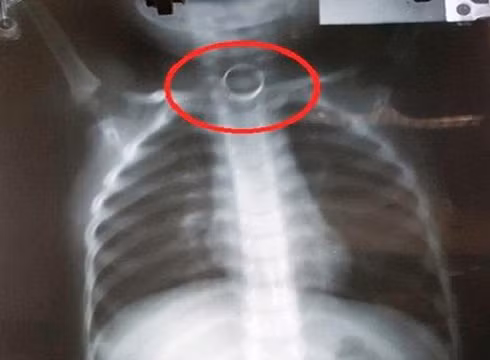

Kết quả khám nghiệm tử thi cho thấy, bên trong thành hầu của bé Y. có một dị vật mềm nhũn (nấm trong cháo) là 2 miếng.

Bên trong cơ thể của bé không có chịu sự tác động của ngoại lực.

Cơ quan Công an đã đưa ra nhận định, bé Y. bị tử vong, do bị ngạt dị vật. Hiện thi thể của bé Y. đã được bàn giao cho gia đình để lo mai táng.